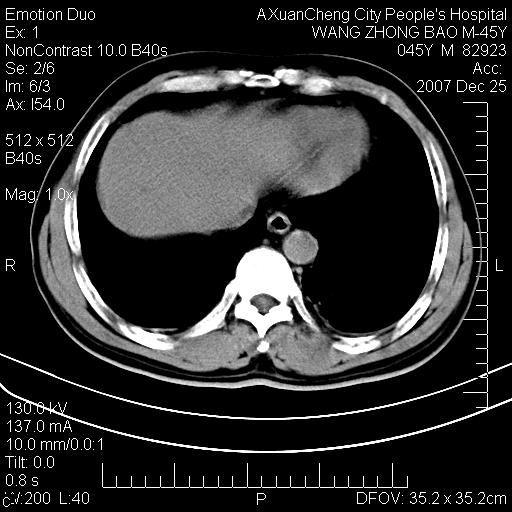

以下是引用qiuleiyu在2007-12-25 18:14:00的发言:[br]胰腺增大,周边渗出改变,肾前筋膜明显增厚,示少量积液.胆囊壁毛糙,周边少许渗出,胆总管壁厚,异常强化,然扩张不明显.结合病程急短;考虑;胆管炎,胆囊炎,胆源性胰腺炎可能大,请结合实验室检查及随访.

以下是引用lisihao在2007-12-25 14:23:00的发言:[br]急性水肿型胰腺炎[br]依据:1、胰腺弥漫性肿大,边缘稍毛糙;[br] 2、双侧肾周筋膜增厚,尤以左侧为甚(重要征象)[br] 3、双侧后胸膜增厚(刺激性炎症);[br] 4、结合病史,查血尿淀粉酶应该可以确诊。